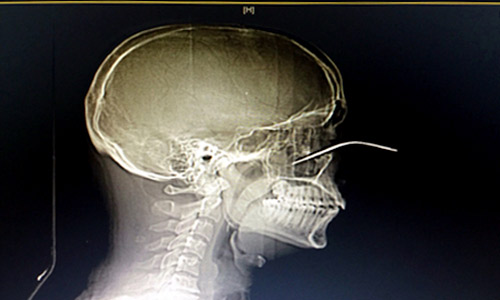

استخرج فريق طبي قسم جراحة الوجه والفكين بمستشفى النور التخصصي بمكة المكرمة في عملية جراحية عاجلة آلة حادة من وجه شاب مقيم، بعد أن استقرت في منطقة ما بين قاع العين والجيب الأنفي من جراء مشاجرة حدثت بينه وبين شاب آخر.

وأوضح اختصاصي جراحة الوجه والفكين بالمستشفى الدكتور حاتم زين الدين، الذي قام بإجراء العملية بإشراف رئيس قسم جراحة الوجه والفكين الدكتور جميل شرقاوي، أن المريض نُقل إلى المستشفى في حالة يرثى لها بعد إصابته بطعنة سكين في وجهه لافتا أنه تم على الفور إجراء الفحوصات ومن ثم إدخاله إلى غرفة العمليات لاستخراج السكين، ومن ثم عمل خياطة تجميلية للعين.